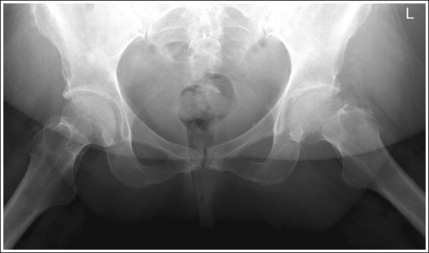

Pelvis: Anteroposterior Projection

See Figures 7-21 and 7-22 and Box 7-5.

The pelvis demonstrates an AP projection. The ischial spines are aligned with the pelvic brim, the sacrum and coccyx are aligned with the symphysis pubis, and the ilia and obturator foramina are open and uniform in size and shape.

• An AP projection of the pelvis is accomplished by placing the patient supine on the imaging table, with the legs extended and the arms drawn away from the pelvic area (Figure 7-23). To ensure that the pelvis is not rotated, judge the distance from the ASIS to the imaging table on each side. The distances should be equal.

• Pelvic rotation. A nonrotated AP pelvis projection demonstrates symmetrical ilia and obturator foramina. Rotation is initially detected by evaluating the relationships of the ischial spines with the pelvic brim and of the sacrum and coccyx with the symphysis pubis. The ischial spines should be aligned with the pelvic brim, and the sacrum and coccyx should be in alignment with the symphysis pubis on a nonrotated pelvis. If the pelvis is rotated into a LPO position, the left ilium is wider than the right, the left obturator foramen is narrower than the right, the left ischial spine is demonstrated without pelvic brim superimposition, and the sacrum and coccyx are not aligned with the symphysis pubis but are rotated toward the right hip (see Image 16).

The femoral necks are demonstrated without foreshortening and the greater trochanters are in profile laterally, whereas the lesser trochanters are superimposed by the femoral necks.

• Accurate leg positioning. To demonstrate the femoral necks without foreshortening and the greater trochanters in profile on an AP pelvis projection, the patient's leg should be internally rotated until the feet are angled 15 to 20 degrees from vertical and the femoral epicondyles are positioned parallel with the imaging table (Figure 7-24; see Figure 7-21). Sandbags or tape may be needed to help maintain this internal leg rotation. An AP pelvis projection may not demonstrate the proximal femurs with exactly the same degree of internal rotation. How each proximal femur appears will depend on the degree of internal rotation placed on that leg.

The inferior sacrum is at the center of the exposure field. The ilia, symphysis pubis, ischia, acetabula, femoral necks and heads, and greater and lesser trochanters are included within the collimated field.

• Center a perpendicular central ray to the midsagittal plane at a level halfway between the symphysis pubis and the midpoint of an imaginary line connecting the ASIS to place the inferior sacrum in the center of the exposure field. Center the IR to the central ray and open the longitudinal collimation the full 14-inch (35-cm) IR length for most adult patients. Transversely collimate to within 0.5 inch (1.25 cm) of the lateral skin line.